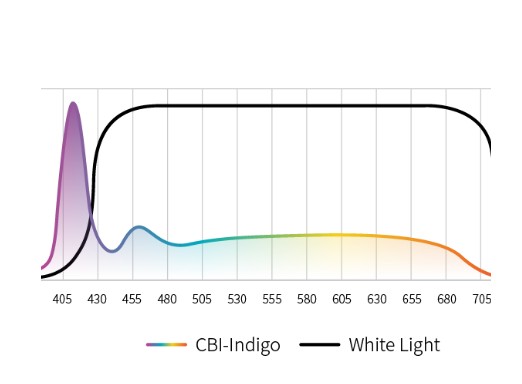

Три режима оптической хромоэндоскопии

Оснащен 4 светодиодными источниками света высокой яркости с независимым управлением, обеспечивающими многоспектральный режим окрашивания «белый свет + 3 спектра CBI». Спектральное окрашивание может повысить визуальный контраст между нормальной тканью и повреждениями, тем самым улучшая выявляемость небольших повреждений. Технология оптического окрашивания (CBI) – удобный и эффективный инструмент для выявления раннего рака, опухолевых и воспалительных процессов.

CBI indigo Усиливает контраст между слизистой оболочкой и кровеносными сосудами. |  |

- CBI indigo — усиление контраста между слизистой и сосудистой сетью.